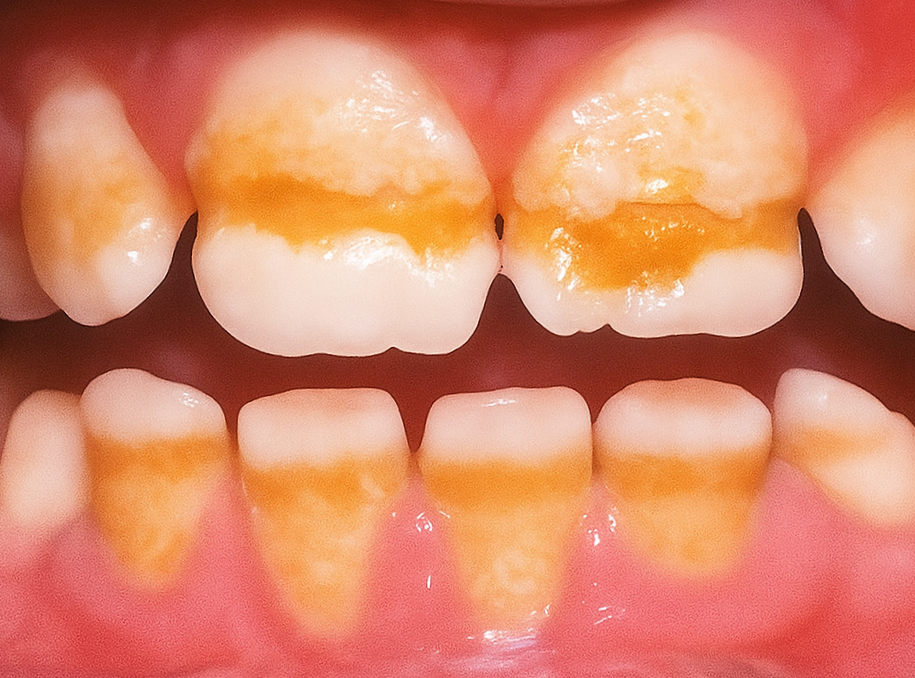

이 질환이 외관에 미치는

영향은 다양합니다.

눈에 띄는 변화는

색깔의 변화입니다.

겉면이 얇아지거나 손상되면

내부의 누런 상아질이 비쳐서

이가 누렇게 보이게 됩니다.

정상적인 자연치의 매끄러운 광택이

사라지고 표면이 거칠어져

막연히 지저분해 보일 수 있습니다.

형태도 변화합니다.

표면에 홈이나 패임이 생기거나

울퉁불퉁한 모양이 되기도 하고,

이가 더 짧고

납작하게 보일 수 있습니다.

심한 경우에는

갈색이나 회색 반점이 나타나기도 하며,

법랑질이 극도로 얇아진 경우

크기가 눈에 띄게

작아질 수도 있습니다.